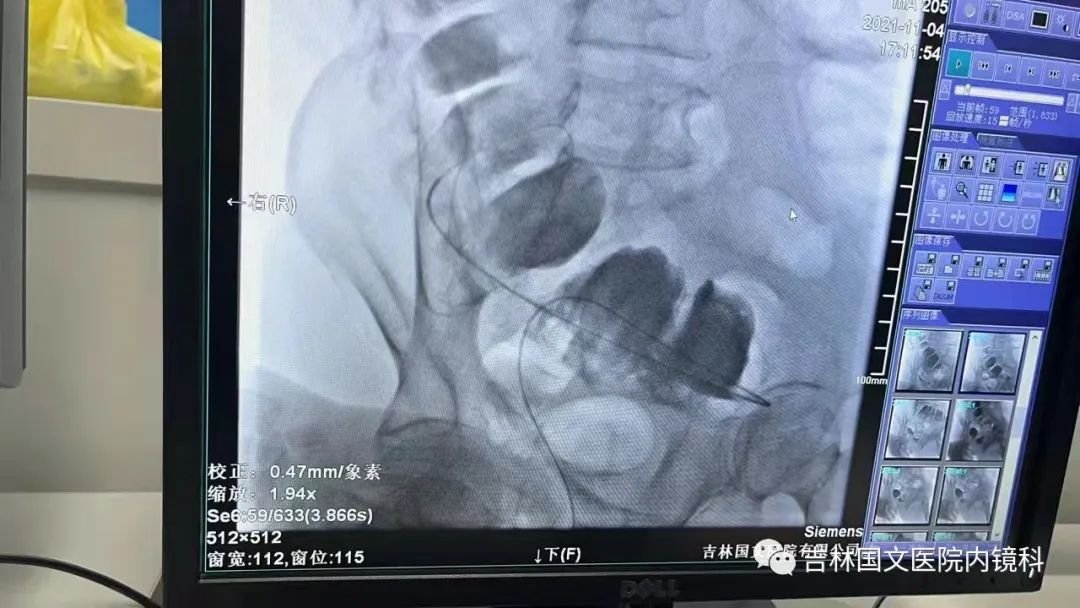

這是一位腸癌的患者,腫物生長在乙狀結(jié)腸,將腸腔堵得只剩一個小孔,糞便自然很難通過,腸梗阻的癥狀使患者十分難受,已多天未排氣排便,患者十分瘦削,開始侯主任未借助任何工具探查一番,結(jié)果就是腸道太迂曲了,實在無法順利將導(dǎo)絲置入,通過邢主任使用腸鏡在前面引路一直到達(dá)病變部位,這時候侯主任將帶有外套管的導(dǎo)絲從活檢口插入,外套管抵在小孔處,導(dǎo)絲順利進(jìn)入,第一步成功。第二步就是將支架順著導(dǎo)絲送入指定位置,又是一大難關(guān),導(dǎo)絲十分軟,缺乏支撐力,腸道的彎曲十分陡峭,一用力支架抵在腸道低處,患者痛感極強(qiáng),只能另想辦法,嘗試多次后,在兩位主任的豐富經(jīng)驗和堅持不懈的努力下,支架順利置入,為患者解除了痛苦。